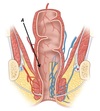

C - Appendix

A - Caecum

B - Mesoappendix